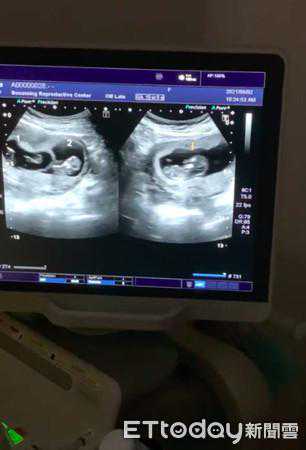

导演明金成开心看到小孩超音波。(图/明金成提供)

52岁导演明金成和圈外老婆明林沛缔(Patty)2017年登记结婚,一路走来求子路艰辛,不断尝试试管婴儿,终于在植入10次有结果,而且是异卵双胞胎,小孩目前近12周,他感动直呼:「第一次从医生口中告知小孩很健康,我就在生殖中心边看萤幕、边用手机录影,一边在哭。」